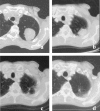

Methods: Fifty-eight patients underwent radiosurgery involving single-dose irradiation. With 25 patients, 31 metastases in the lungs were irradiated; with each of 33 patients, stage I non-small cell lung cancer (NSCLC) was subject to irradiation. The standard dose prescribed to the isocenter was 30 Gy with an axial safety margin of 10 mm and a longitudinal safety margin of 15 mm. The planning target volume (PTV) was defined using three CT scans with reference to the phases of respiration so that the movement span of the clinical target volume (CTV) was enclosed.

Results: The volume of the metastases (CTV) varied from 2.8 to 55.8 cm3 (median: 6.0 cm3) and the PTV varied from 12.2 to 184.0 cm3 (median: 45.0 cm3). The metastases ranged from 0.7 to 4.5 cm in largest diameter. The volume of the bronchial carcinomas varied from 4.2 to 125.4 cm3 (median: 17.5 cm3) and the PTV from 15.6 to 387.3 cm3 (median: 99.8 cm3). The bronchial carcinomas ranged from 1.7 to 10 cm in largest diameter. Follow-up periods varied from 6.8 to 63 months (median: 22 months for metastases and 18 months for NSCLC). Local control was achieved with 94% of NSCLC and 87% of metastases. No serious symptomatic side effects were observed. According to the Kaplan-Meier method the overall survival probability rates of patients with lung metastases were as follows: 1 year: 97%, 2 years: 73%, 3 years: 42%, 4 years: 42%, 5 years: 42% (median survival: 26 months); of those with NSCLC: 1 year: 83%, 2 years: 63%, 3 years: 53%, 4 years: 39%: (median survival: 20.4 months).